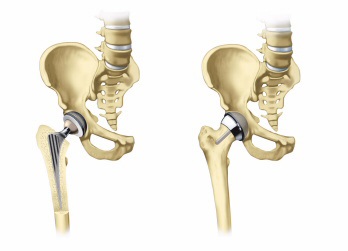

A csípőízület olyan, mint egy labdát az üregbe. csípőízületi üreg nevezik csípőizületbe. Combfej forog, így a konkáv felülete a csípőizületi vápa.

A protézis csípő izületi vápa, amely egy fém héj egy műanyag vagy fém béléssel. A törzs a protézis behelyezésekor be a vastagsága a combfej és mesterséges protézis - a csípőizületi vápa.